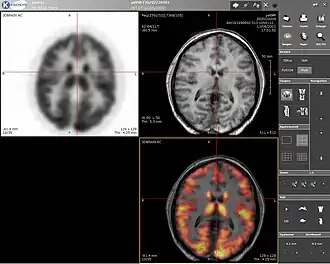

Computer screenshot showing a PET image (upper left), an MRI image (upper right), and the combined PET–MRI image where PET data is overlaid over the MRI data (lower right) | |

Positron emission tomography–magnetic resonance imaging (PET–MRI) is a hybrid imaging technology that incorporates magnetic resonance imaging (MRI) soft tissue morphological imaging and positron emission tomography (PET) functional imaging.[1]